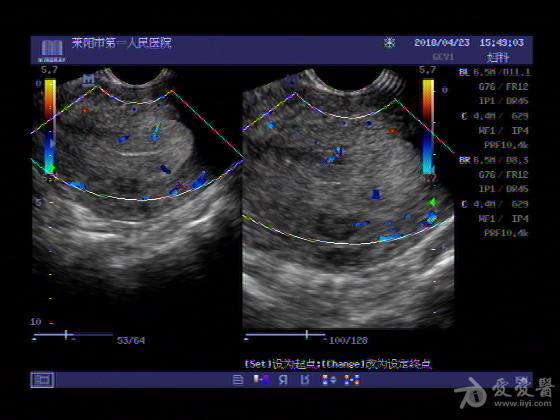

女,48岁,月经量多,两个月,一年前出现过类似现象,刮宫吃药后缓解。

超声可见:子宫内膜显著增厚,后肌壁内膜可见范围约3.27X0.90CM低回声区,CDFI显示较丰富线样血流,宫底宫腔内见类**状低回声结节。前肌壁见多发类圆形低回声结节。

超声提示:子宫内膜增厚(建议刮宫病理),子宫多发肌瘤

病理结果:内膜增生